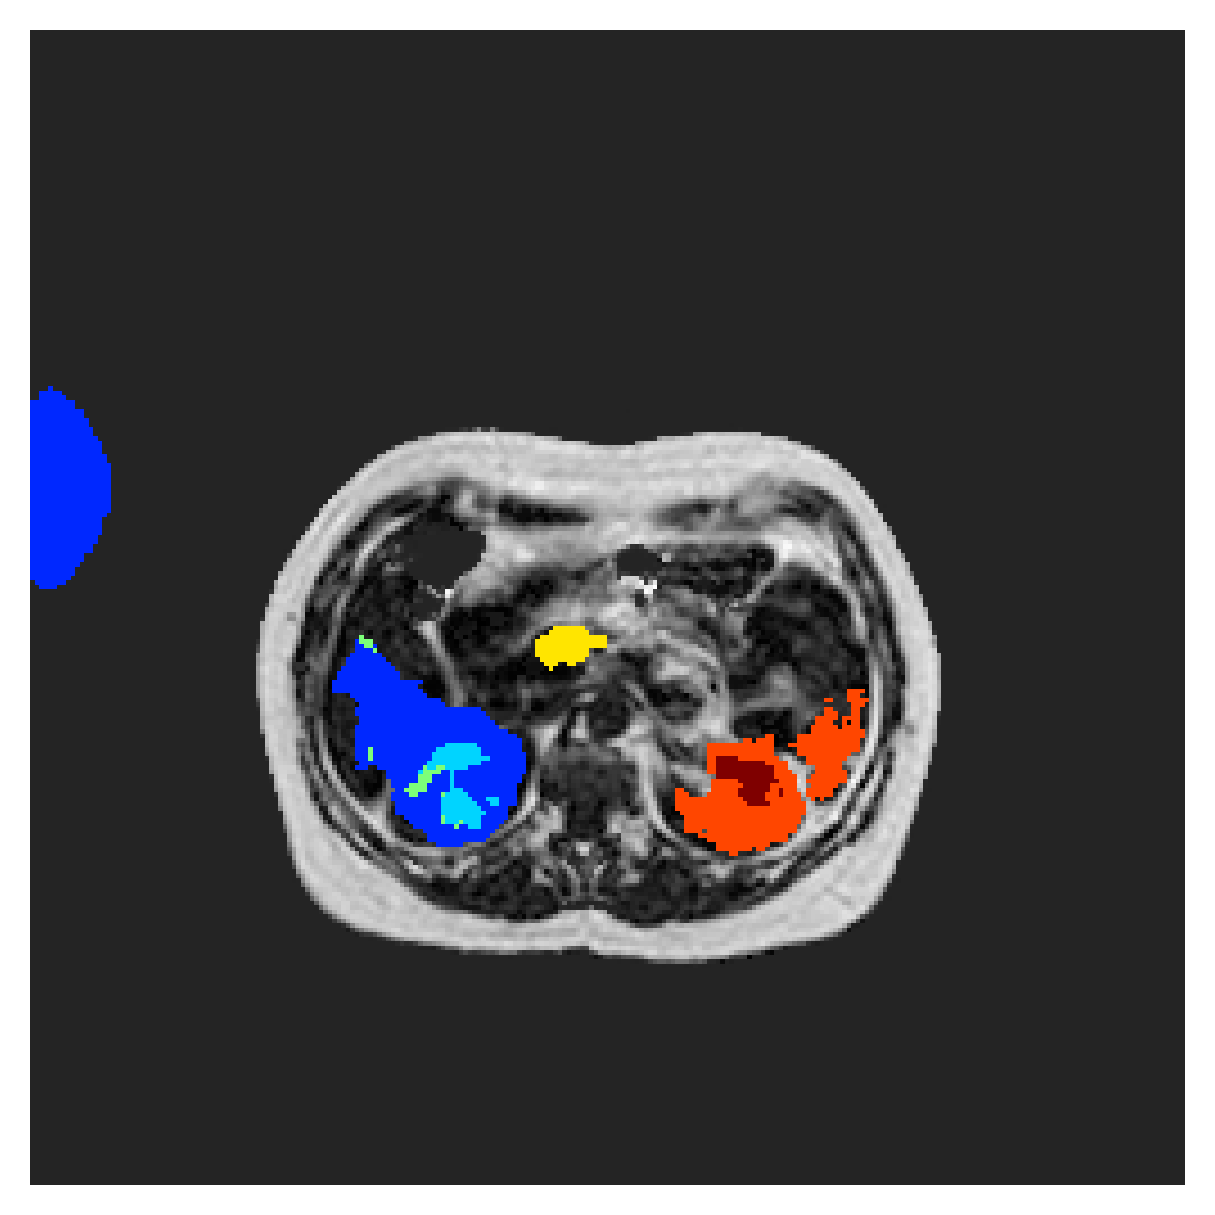

In Figure 6 we provide qualitative results on a number of randomly chosen test set slices. Upon visual inspection, we can observe that training with the intensity-aware distances (particularly with and ) follows the image gradients better and is better at recovering the underlying shape than the Euclidean version. The CRF-loss seems to recover the shape of the myocardium and left ventricle to some extent, but fails entirely on the right ventricle.

5.2 Abdominal organ segmentation

Using 2D distance maps

In Table 3, the average DSC and HD95 results are shown (both using 2D and 3D distance maps) for the task of abdominal organ segmentation in POEM data (for boxplots see figures 8 and 9). We see that training with and (with distances calculated on 2D slices) performs comparably, while using and produces lower scores in both DSC and HD95 metric. On this dataset, the CRF-loss is able to compete with the boundary loss-based training strategies, even outperforming them on most classes. Most notably, all models trained with boundary loss appear to have a hard time segmenting the liver. We hypothesize this may be due to extremely severe class imbalance, as the liver covers a very large area compared to the rest of the classes. It is thus also more strongly affected by undersegmentations.

5.2.1 Qualitative comparison

In Figure 11 and 12 we show the same random slices in cases of calculating the boundary loss on 2D- and 3D-based distances, respectively. Comparing the two figures again indicates that the intensity-aware distances offer most improvement when calculated in 3D over 2D. The exception here is the MBD, which seems to even slightly degrade for most classes.